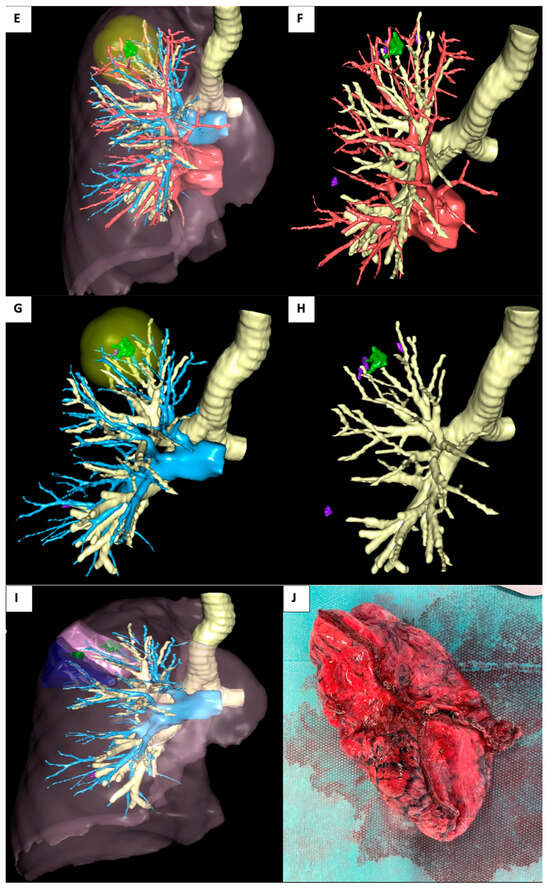

2.1. Case 1